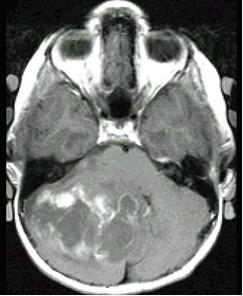

颅后窝肿瘤(如图所示)临床症状应除外()

[单选题]颅后窝肿瘤(如图所示)临床症状应除外 ( )A.轮替试验幅度增大B.躯干性和下肢远端的共济失调C.交叉性麻痹D.Romberg征多为阴性E.同侧后组脑